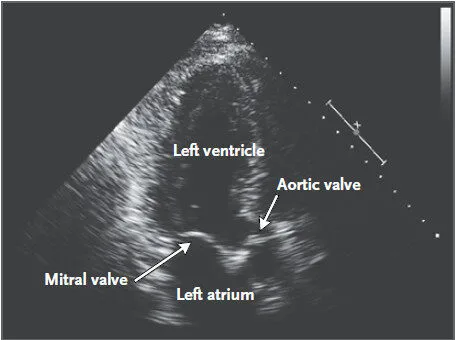

该病患者出现心脏杂音,通常表示感染已累及到心脏,患者行超声心动图检查,见图 3。

图 3 :经食管超声心动图显示主动脉瓣上有团块,7*6 mm。轻度主动脉狭窄,肺动脉压力测不出。

患者血培养阴性,未出现发热等症状。给患者静脉注射头孢曲松钠 2 周,之后口服复方磺胺甲恶唑,每天两次。2 个月之后患者咳嗽、关节痛和肌痛症状都有所缓解。再次行超声心动图检查发现主动脉瓣上赘生物几乎消失,见图 4 。

图 4 :抗生素治疗 6 个月之后已经看不见主动脉瓣上的赘生物